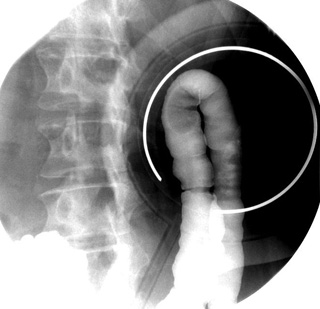

BE LPO patient positionBE Hepatic Flexure spot